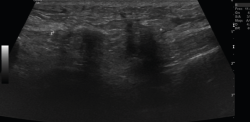

Ecografía

El ultrasonido se puede usar en el diagnóstico de numerosas patologías y puede guiar en procedimientos diagnósticos y terapéuticos(5).

Su indicación fundamental es en el diagnóstico de las lesiones de partes blandas superficiales.

Las estructuras específicas más adecuadas para este estudio incluyen tendones, músculos y ligamentos, además de masas periarticulares de tejidos blandos. Es útil para el diagnóstico de derrame articular, engrosamiento sinovial, bursitis, cuerpos libres intraarticulares, gangliones, quistes, roturas ligamentosas y tendinosas, tendinitis y fracturas ocultas(6).

En el estudio musculoesquelético se utiliza una sonda lineal con alta frecuencia, de entre 9 y 13 mHz.

2. Tendones

2.1. Tendinitis

Con ecografía Doppler pueden aparecer áreas de hiperemia intratendinosa o peritendinosa (Figura 8).

Figura 8. Corte sagital de una ecografía de rodilla del tendón rotuliano: engrosamiento del tendón con aumento difuso de ecogenicidad.

2.2. Roturas

Se observan áreas hipoecoicas de solución de continuidad de las fibras tendinosas(7), con retracción de los márgenes con la contracción muscular cuando la rotura tendinosa es completa (Figuras 9 y 10).

Figura 9. Corte sagital de una ecografía de rodilla: foco hipoecoico por rotura parcial del tendón cuadricipital.

Figura 10. Corte sagital de una ecografía de rodilla: ausencia del tendón rotuliano por rotura completa, con hematoma señalado en el trayecto del tendón.